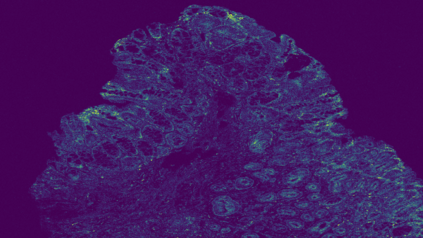

The usage of chemical imaging technologies is becoming a routine accompaniment to traditional methods in pathology. Significant technological advances have developed these next generation techniques to provide rich, spatially resolved, multidimensional chemical images. The rise of digital pathology has significantly enhanced the synergy of these imaging modalities with optical microscopy and immunohistochemistry, enhancing our understanding of the biological mechanisms and progression of diseases. Techniques such as imaging mass cytometry provide labelled multidimensional (multiplex) images of specific components used in conjunction with digital pathology techniques. These powerful techniques generate a wealth of high dimensional data that create significant challenges in data analysis. Unsupervised methods such as clustering are an attractive way to analyse these data, however, they require the selection of parameters such as the number of clusters. Here we propose a methodology to estimate the number of clusters in an automatic data-driven manner using a deep sparse autoencoder to embed the data into a lower dimensional space. We compute the density of regions in the embedded space, the majority of which are empty, enabling the high density regions to be detected as outliers and provide an estimate for the number of clusters. This framework provides a fully unsupervised and data-driven method to analyse multidimensional data. In this work we demonstrate our method using 45 multiplex imaging mass cytometry datasets. Moreover, our model is trained using only one of the datasets and the learned embedding is applied to the remaining 44 images providing an efficient process for data analysis. Finally, we demonstrate the high computational efficiency of our method which is two orders of magnitude faster than estimating via computing the sum squared distances as a function of cluster number.